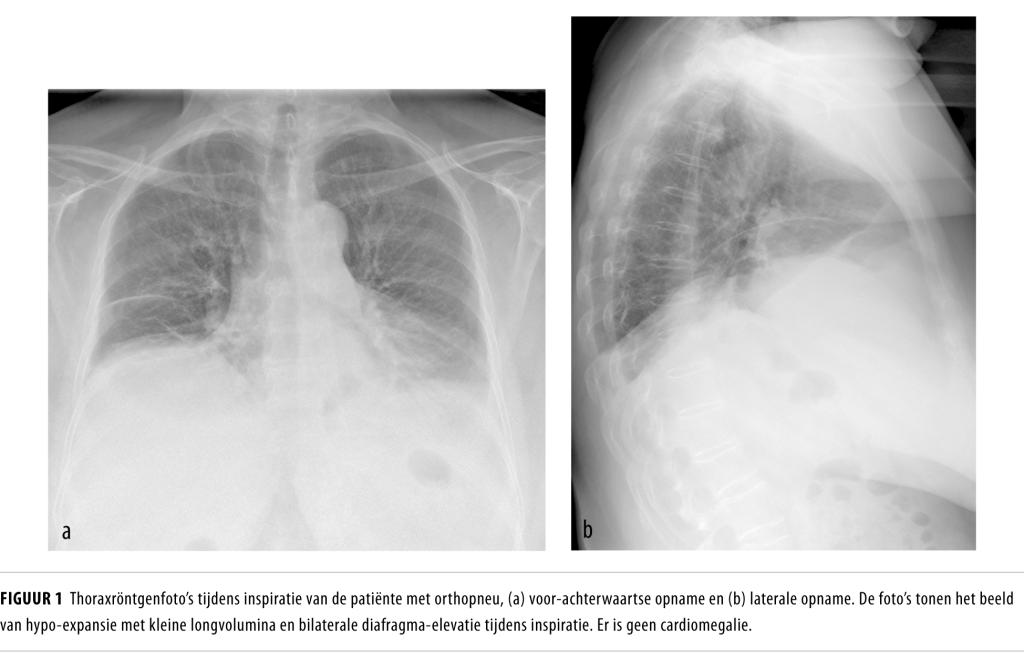

Wij zagen een 67-jarige vrouw wegens plotse orthopneu. Beeldvormend onderzoek toonde bilaterale diafragmaparalyse en emg bevestigde neuropathie van beide Nn. phrenici. De diagnose luidde ‘bilaterale neuralgische amyotrofie’. Patiënte kreeg nachtelijke ondersteuning van de ademhaling in de vorm van zuurstoftherapie met hoge nasale flow. Deze symptomatische behandeling had een goed effect.

Neuralgische amyotrofie wordt gekenmerkt door pijn in de nek of schouderregio, gevolgd door zowel motorische als sensorische neuropathie van de plexus brachialis. De incidentie wordt geschat op 1 op de 1000 per jaar. Bij een zeldzame variant van dit ziektebeeld zijn beide Nn. phrenici aangedaan, waardoor diafragmaparalyse en ernstige orthopneu ontstaan.